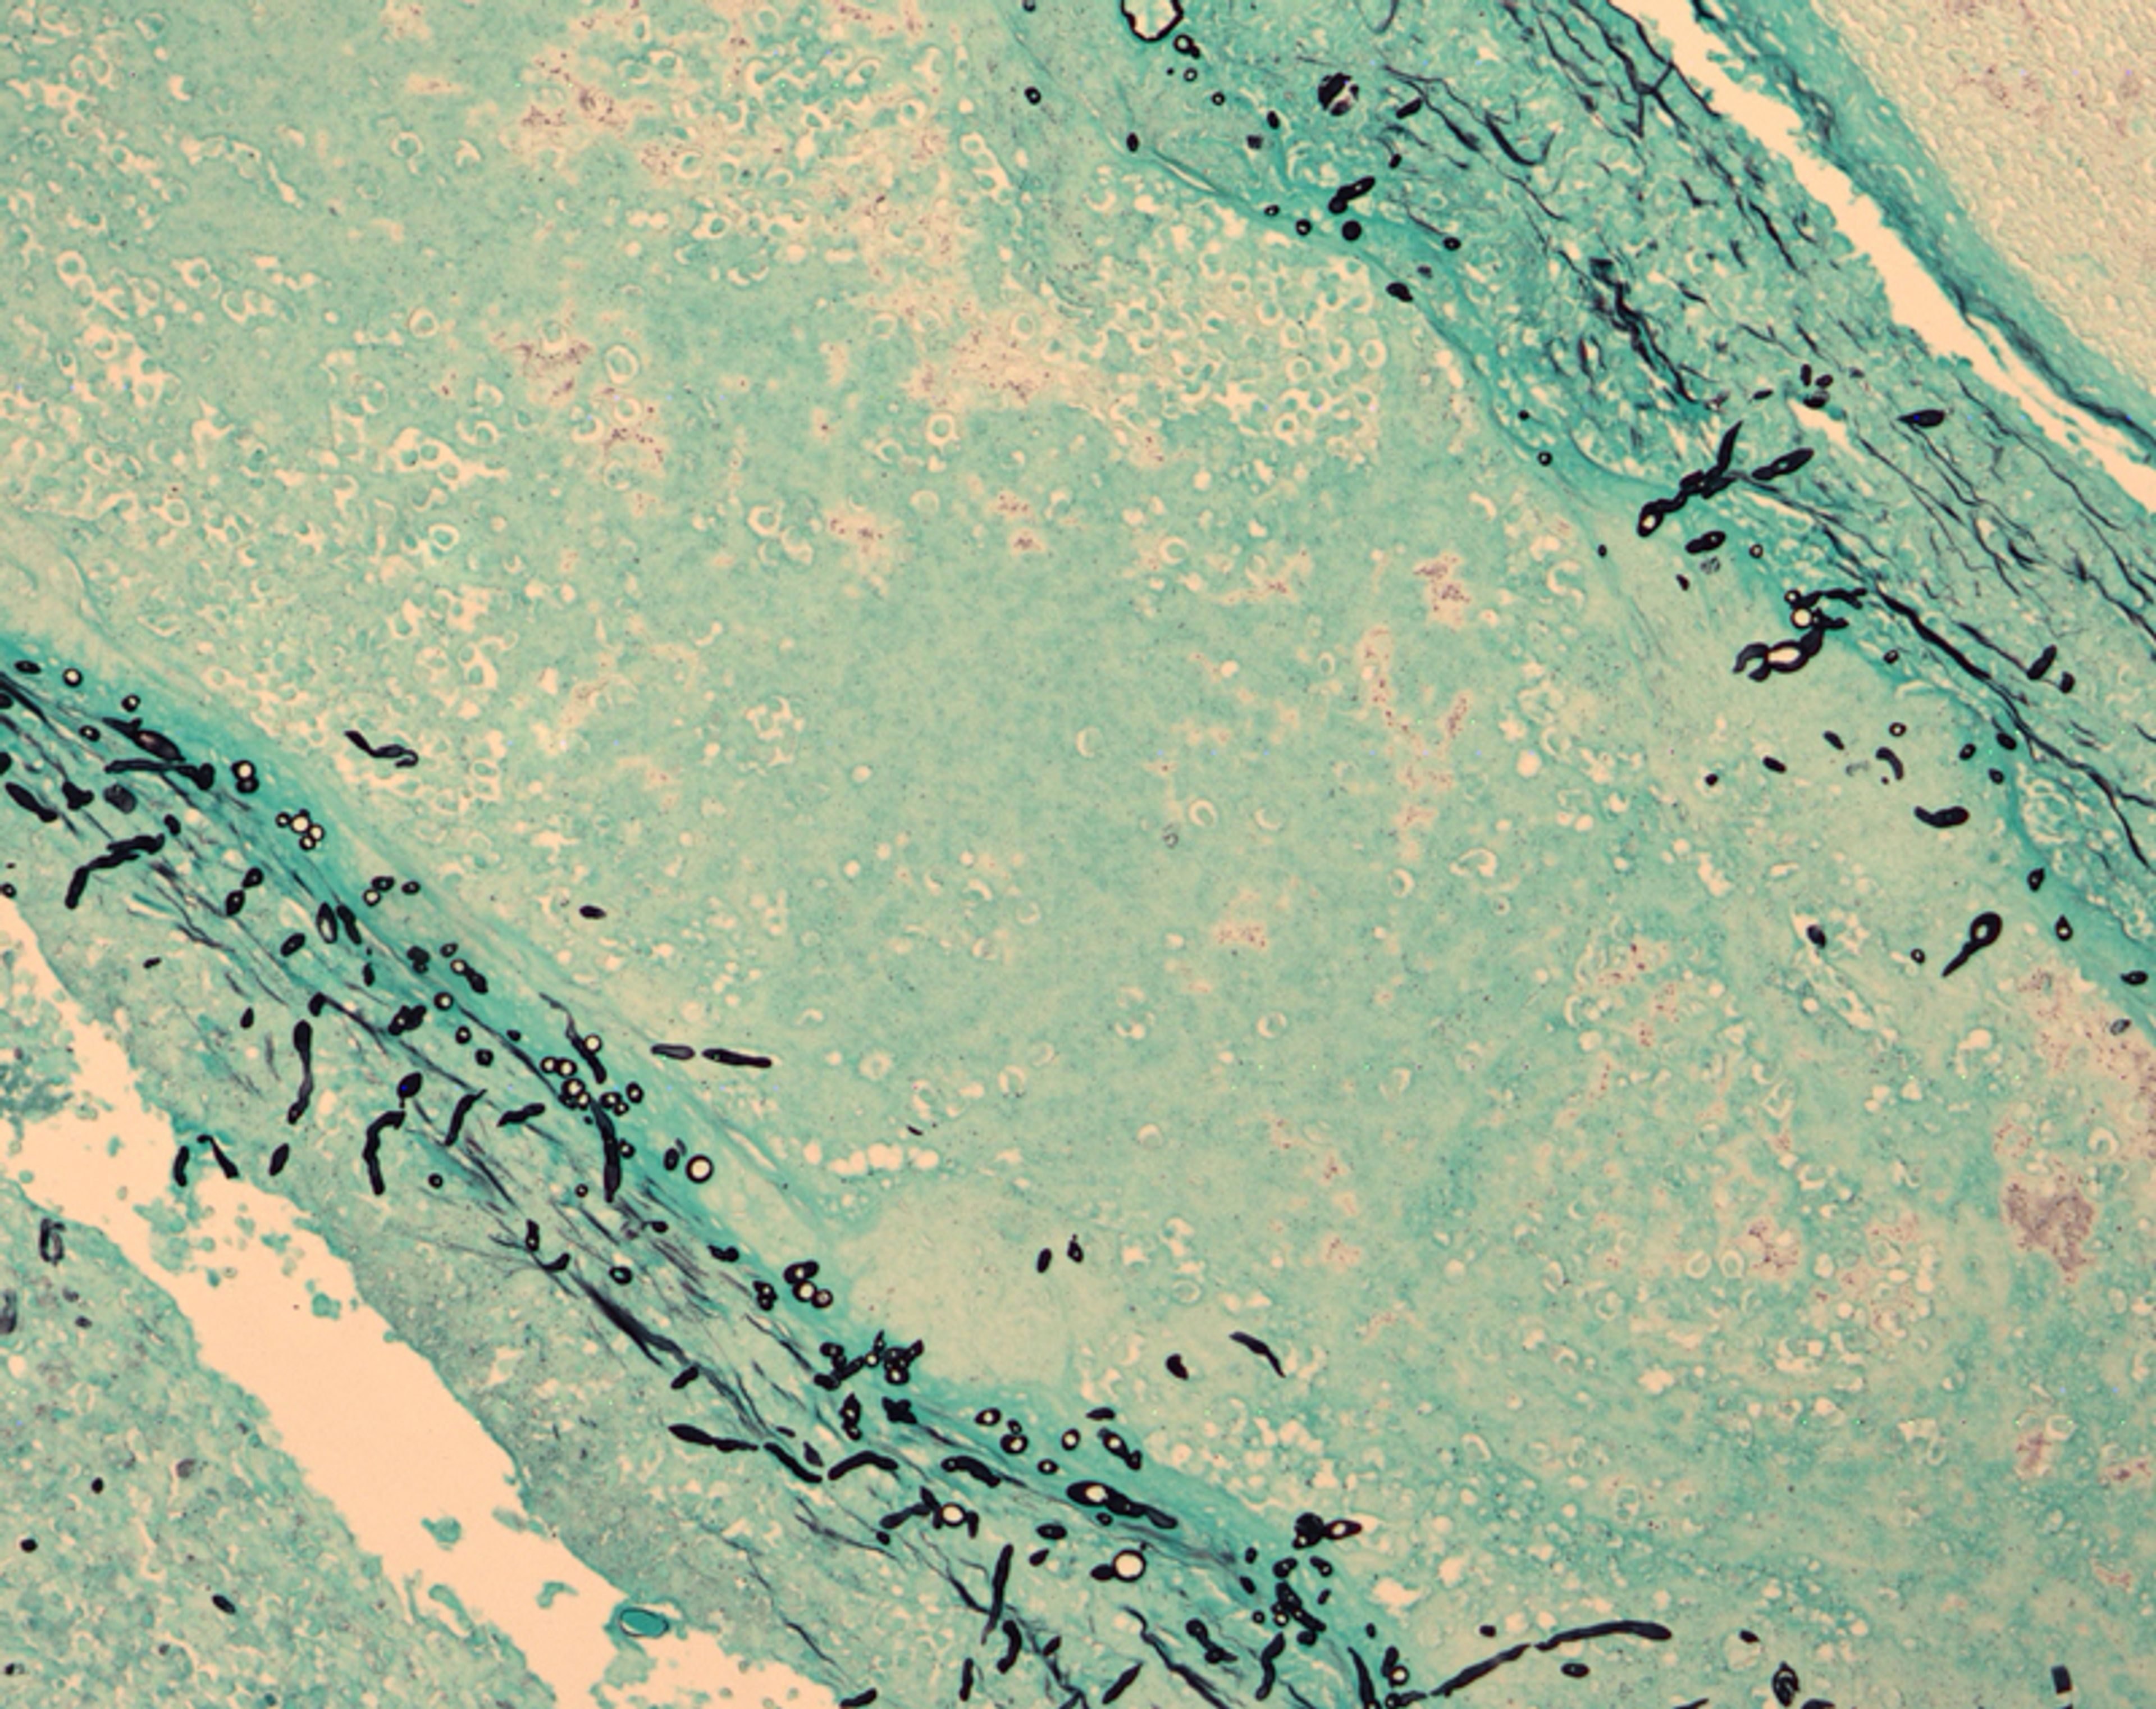

El Centro de Compuestos de Nueva Inglaterra fue una farmacia en Massachusetts que produjo inyecciones de esteroides defectuosas. Las dosis contaminadas causaron infecciones fúngicas graves en cientos de pacientes en varios estados.

En septiembre de 2012, los investigadores federales identificaron la instalación como la fuente de medicamentos esteroides contaminados que infectaron a casi 800 pacientes y causaron más de 100 muertes. El escándalo provocó una revisión exhaustiva de los procedimientos de inspección y seguridad de las farmacias en todo el país.